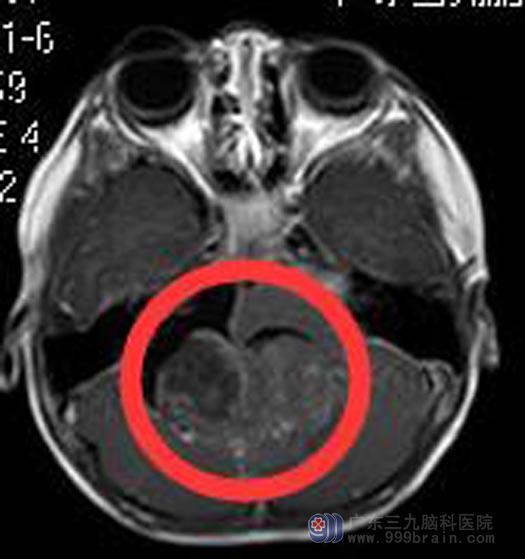

广东三九脑科医院头颅MR检查提示:小脑蚓部一团块状占位性病变,大小约5.7cm×5.4cm×4.2cm,小脑扁桃体受累并变尖,下端呈舌状,向下疝入椎管内,达C2水平;延髓受压前移。

▲手术前